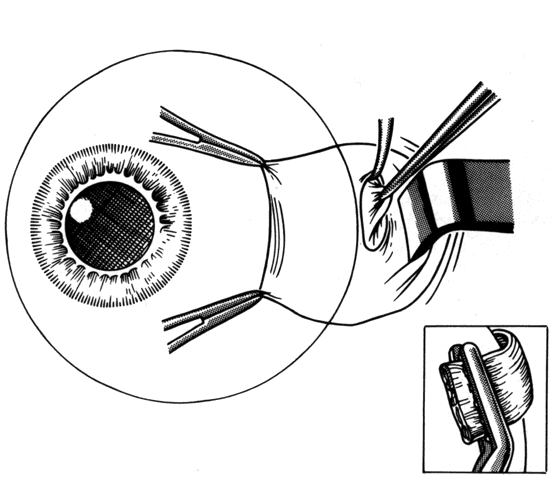

If a muscle has been lost, or has slipped from its original insertion, or when only the muscle capsule is attached to the globe and the actual muscle tissue has slid back through the muscle sleeve, the force generated by the muscle will be greatly diminished. Effort must be directed to finding and recovering the muscle tissue and reattaching it to the globe, thus restoring the contractile force of the muscle. Once disinserted, the most difficult muscle to find is the medial rectus muscle. This is because once the intermuscular membranes are cut, it has no attachments to other muscles and it can retract into the orbit. The other rectus muscles have attachments to other muscles that facilitate recovery. The superior rectus is attached to the superior oblique, the inferior rectus is attached to the inferior oblique, and the lateral rectus has attachments between the undersurface of the lateral rectus and the orbital surface of the inferior oblique. Once these attachments are identified, the small operculum in Tenon's capsule, through which the muscle sleeve passes, can usually be identified. When this operculum has been found, a forceps is used to grasp muscle tissue. If the patient has not been given atropine, bradycardia may occur when traction is applied to muscle tissue. It is important to avoid pulling Tenon's fascia forward in a blind attempt to find the muscle. This may cause the muscle to further retract from the opening in Tenon's capsule. It is preferable to gently displace the globe away from the area of surgical exploration with blunt retraction; vigorous rotation of the globe may cause further posterior slippage of the lost muscle. Once the muscle has been identified, it is helpful to place a locking Castroviejo forcep on the muscle or its tendon. This will reduce the chance that the recovered muscle will inadvertently slip out of the instrument and retract into the orbit. A hand-over-hand technique can be used to bring the remainder of the muscle tissue anterior. Once the muscle is brought anterior, a Jameson resection clamp can be applied to the muscle tendon. When a suture has been placed through the muscle, the clamp is removed (Fig. 41). The muscle can then be reattached to the globe in a position that, in the surgeon's best judgment, will provide the best alignment.

Fig. 41. When a muscle slips out of a clamp, becomes disinserted from its tendon, or is “lost,” it can be found by searching along the scleral surface to find an operculum in Tenon's capsule. Once muscle tissue is identified, it is brought handover-hand through the operculum and placed on a secure clamp such as a Jameson resection clamp.